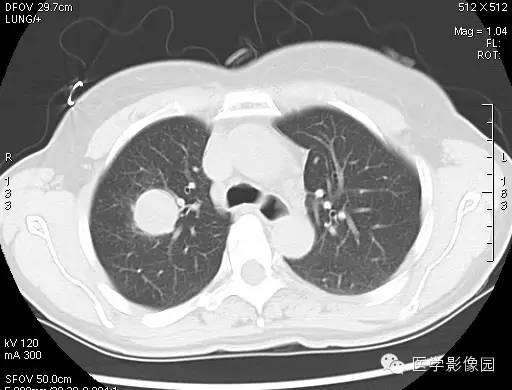

CT 平扫,肿块和软组织的密度很相似,单发性的PSH肿块形状为圆形 或类圆形,肿块的密度均匀,边缘也清晰可见。